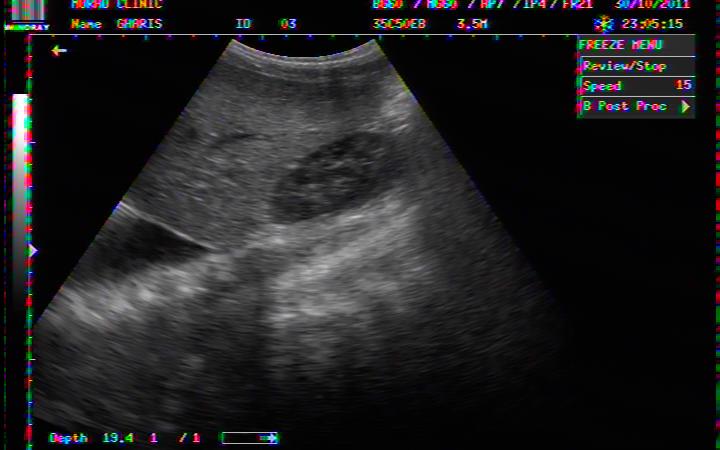

BILATERAL PLEURAL EFFUSION IN A 03 YEARS OLD BOY WITH DHF

BILATERAL PLEURAL EFFUSION COMPLETELY REABSORBED AFTER 3 WEEKS